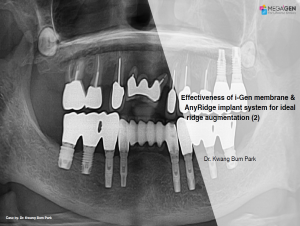

Keywords

e.g. product name, treatment solution, author, clinician name